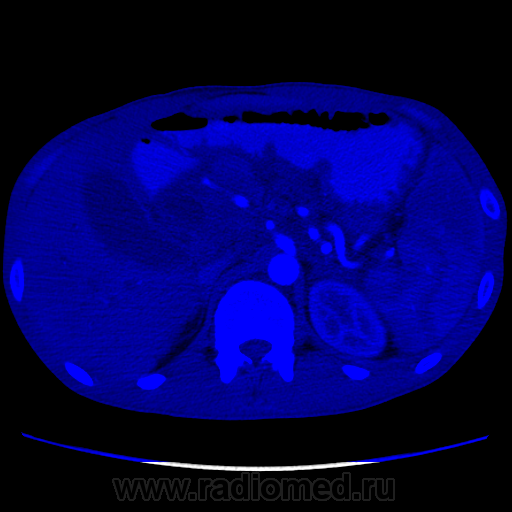

Видео крутит быстро. В головке плджелудочнгой железы кистозное образование с неравномерной толщины капсулой, наличием перегородок и солидного компонента. Печёночные желчные протоки, холедох значительно расширины. Вирсунгов проток расширен. Начальные отделы воротной вены сужены, возможно есть прорастание, не могу уследить. Итого: макрокистозная цистаденома (возможно уже цистаденокарцинома)

Не вижу, честно говоря, ни перегородок, ни солидного компонента. Вижу несколько (кажется, 3, но крутит очень быстро) кистозных образования в головке поджелудочной с относительно равномерно утолщенной капсулой. Плюс - неравномерное расширение Вирсунгова протока, инфильтрация перипанкреатической клетчатки и выпо в брюшной полости. Все укладывается в картину хронического панкреатита в стадии обострения с образованием псевдокист в головке железы.

Молодой человек никогда не болел панкреатитами, спросил были ли периоды сильных болей в животе вообще - говорит "не припомню", не выпивающий и тп. Сейчас клиника - боли, плохие анализы биохимии крови (не помню уже какие). Для псевдокист всё подходит, кроме клиники... Не очень представляю я себе, чтобы такой бессимптомный острый процесс, который тут якобы был, который сформироваться бы в такие псевдокисты... Причем самая крупная киста достаточно прилично деформирует прилежащие структуры, что тоже далеко не частое явление при псевдокистах. Далее... Капсула(псевдокапсула) довольна толстая, в артериальную фазу в ней мелькают маленькие артериальные сосуды. В настоящий момент изменения по типу "панкреатита" могут быть вторичными. В общем, не знаю. Почти убедили, что это псевдокисты. Как быть с анамнезом - сомнительно. Все врут.